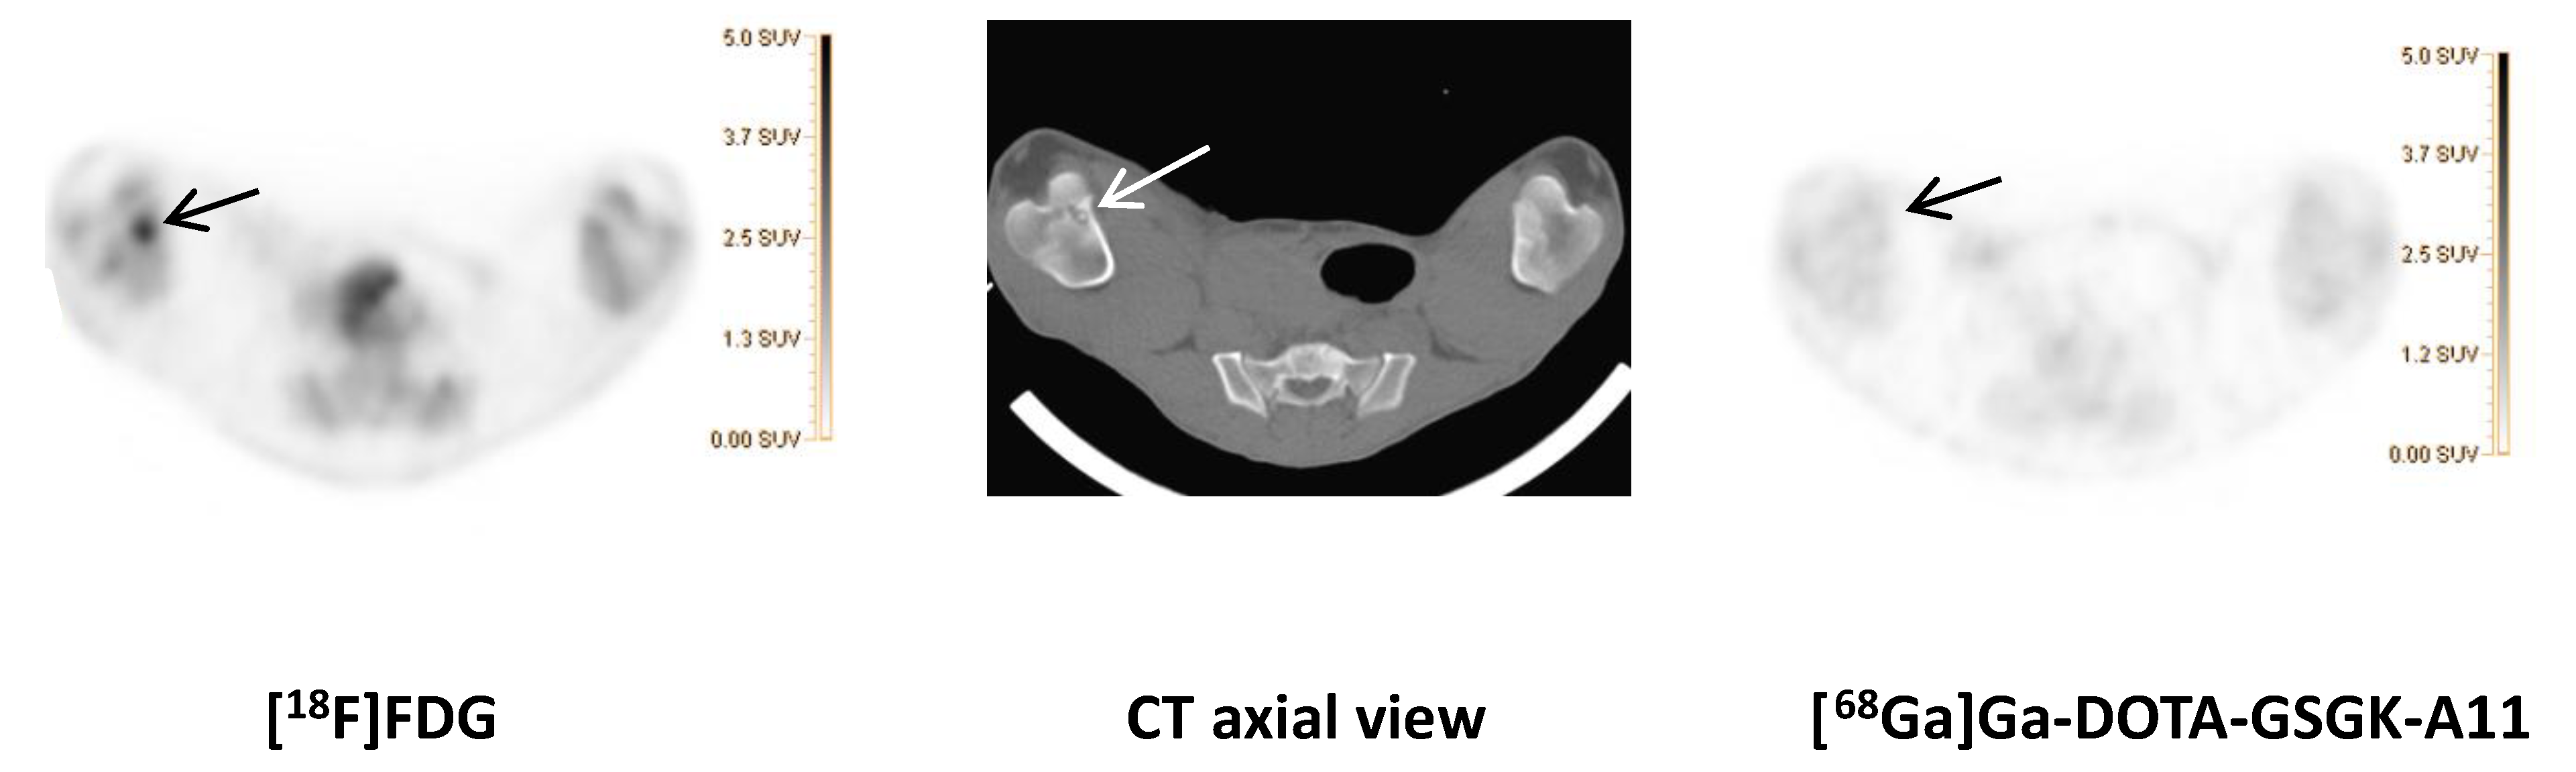

While previous evaluation in murine subcutaneous S. aureus infections showed uptake of [68Ga]Ga-DOTA-K-A9 [9,14], we saw no increased tracer activity of the two S. aureus phage displayed selected peptides, [68Ga]Ga-DOTA-K-A9 (Figure 1) and [68Ga]Ga-GSG-KA-11 (Figure 2) in 9 and 5, respectively, porcine OM lesions. Figure 3 shows the bio-distribution of the peptides in pigs. Both peptides were excreted by the liver and kidneys.

[18F]FDG (left) and Ga-DOTA-K-A9 (right) accumulation is shown in an OM lesion in the right calcaneus and distal II metatarsus of pig 4 (indicated by arrows). The lesions show sequester formation and lysis of the cortical bone on CT in the axial view (middle). Comparable SUV scales are shown to the right of the PET images.

[18F]FDG (left) and [68Ga]Ga-DOTA-GSGK-A11 (right) accumulation in the right distal femur of pig 7. An OM lesion close to the medial part of the growth zone of the distal right femur with sequester formation and lysis of the cortical bone was revealed on the axial CT image (middle). Comparable SUV scales are shown to the right of the PET images.